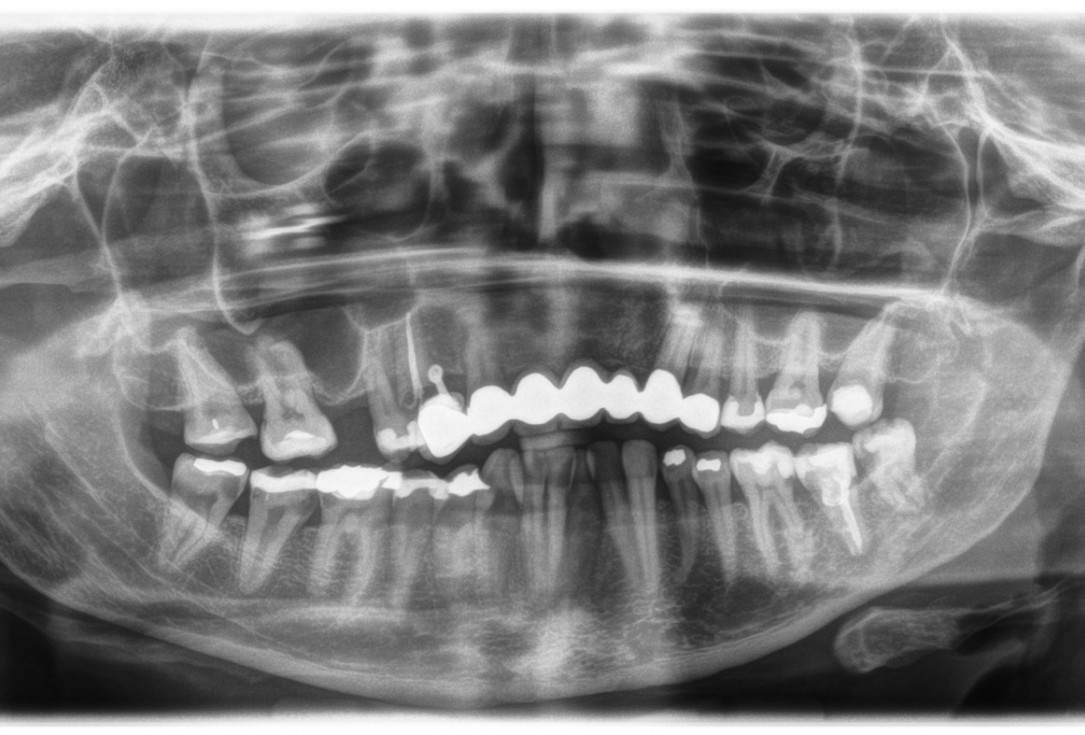

Initial situation 57-year old female patient. X-ray scan reveals severe bone loss due to inflammation in region 13. Treatment plan was extraction of teeth 13 and 14 and augmentation after healing.